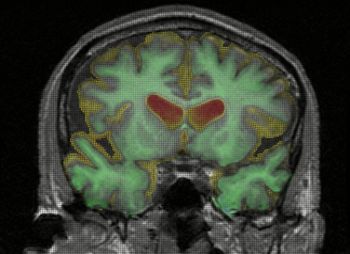

A sinistra la sezione di un cervello normale, a destra quella di un cervello colpito da Alzheimer.Il cervello è una enorme rete di comunicazione, che contiene più di 100 miliardi di cellule nervose (neuroni), con ramificazioni che si connettono in più di...